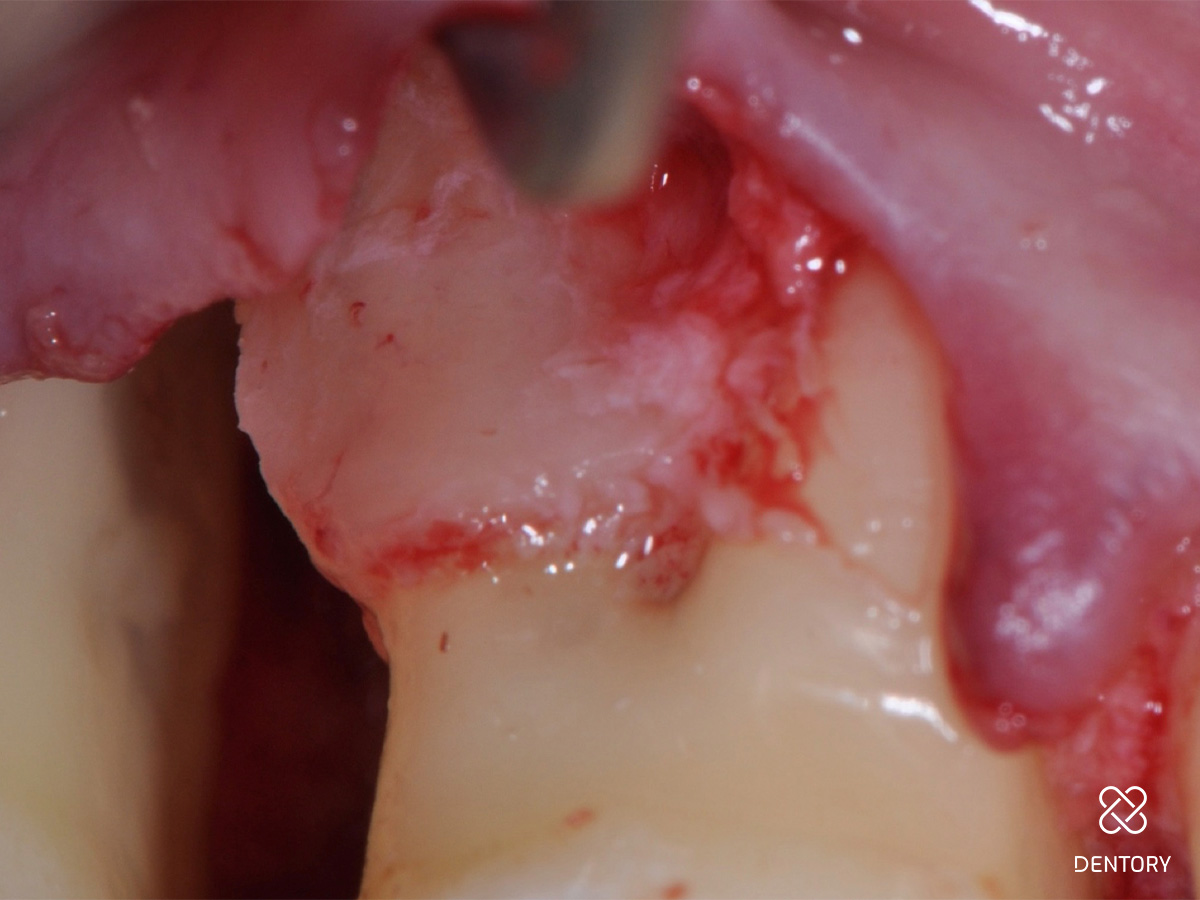

Abbildung 5

Mit einem feinen Raspatorium oder einem Papillenelevator wird ein Mukoperiostlappen zur Darstellung der knöchernen Strukturen präpariert. Die Präparation beginnt idealerweise von einer gut tastbaren Knochenkante zum Defekt hin.